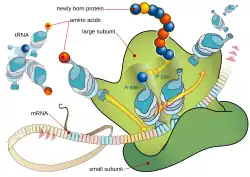

Оксазолидиноны являются ингибиторами синтеза белка: они останавливают рост и размножение бактерий, нарушая трансляцию белков на рибосомах. Хотя механизм действия полностью не понятен,[86] линезолид, вероятно, действует на первом этапе синтеза белков — инициации — в отличие от большинства других ингибиторов синтеза белка, которые препятствуют элонгации.[81][87]

Препарат делает это путём предотвращения образования инициирующего комплекса, состоящего из 30S и 50S субъединиц рибосомы, тРНК и мРНК. Линезолид связывается с 23S частью 50S субъединицы (центр действия пептидилтрансферазы),[88] рядом с областью связывания хлорамфеникола, линкомицина и других антибиотиков. В связи с этим уникальным механизмом действия, перекрёстная резистентность между линезолидом и другими ингибиторами синтеза белка возникает очень редко или вовсе отсутствует.[5][26]

В 2008 году кристаллическая структура линезолида, связанная с 50S субъединицей рибосомы архея Haloarcula marismortui, была выделена группой учёных из Йельского университета и хранится в Protein Data Bank.[89] Другая группа учёных в 2008 году определила структура линезолида, связанного с 50S субъединицей Deinococcus radiodurans. Авторы предложили уточнённую модель механизма действия оксазолидинонов, установив, что линезолид занимает А область 50S рибосомной субъединицы, вызывая конформационные изменения, что предотвращает попадание тРНК и, в итоге, заставляя тРНК отделиться от рибосомы.[90]